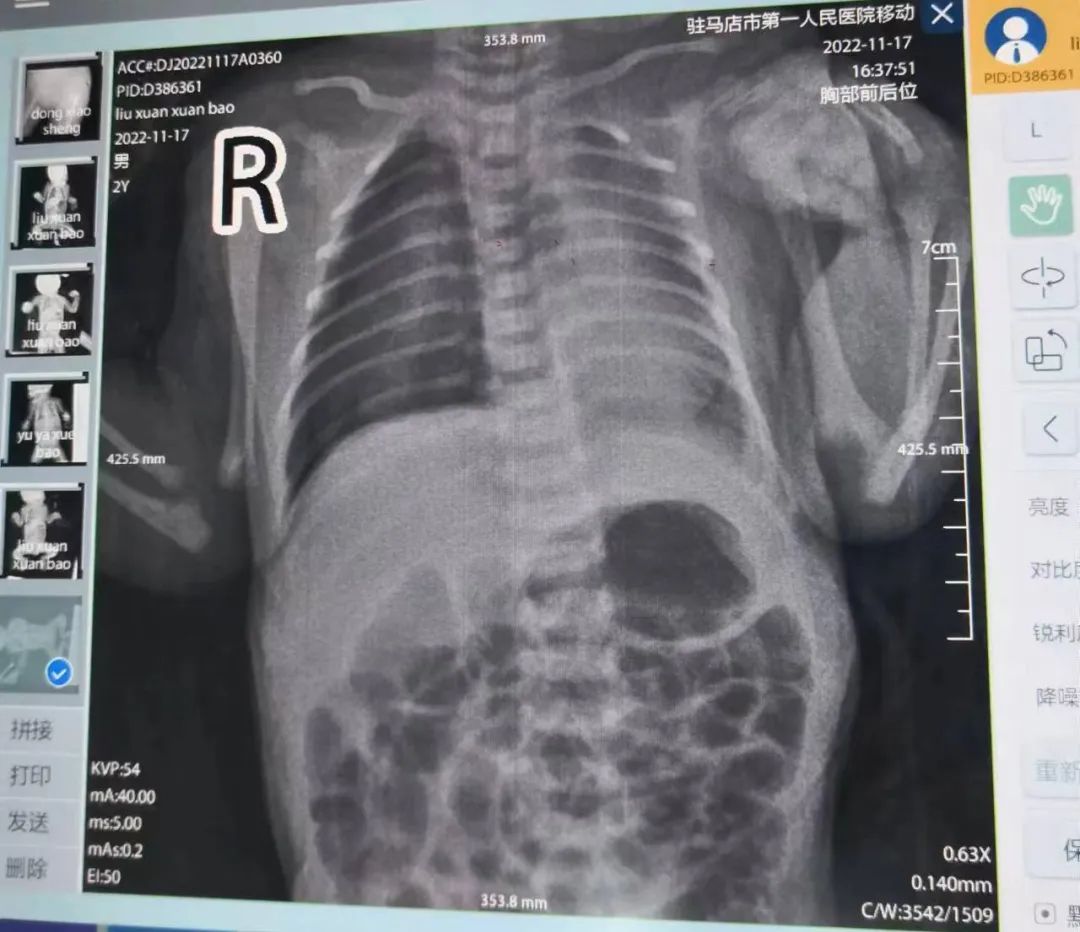

该宝宝出生1小时即出现皮肤青紫、呼吸困难,患儿立即转入新生儿科,考虑可能存在肺部疾病,急查床旁胸片提示存在肺炎并发气胸,且肺部压缩30%以上,主管医师紧急给予气管插管、机械通气。

时间就是生命,王娟主任当机立断,立即请心胸外科会诊,并与家属详细沟通病情。17日在心胸外科李方军主任医师指导下,给予患儿行“胸腔穿刺术”,术中引流出气体30毫升,术后严密监测生命体征及病情变化。

治疗第3天,复查胸片显示气胸明显吸收好转,大家始终悬着的心终于落地。经过10余天的精心治疗和护理,患儿终于顺利康复出院。